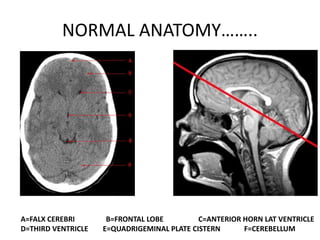

NORMAL ANATOMY……..

A=FALX CEREBRI B=FRONTAL LOBE C=ANTERIOR HORN LAT VENTRICLE

D=THIRD VENTRICLE E=QUADRIGEMINAL PLATE CISTERN F=CEREBELLUM